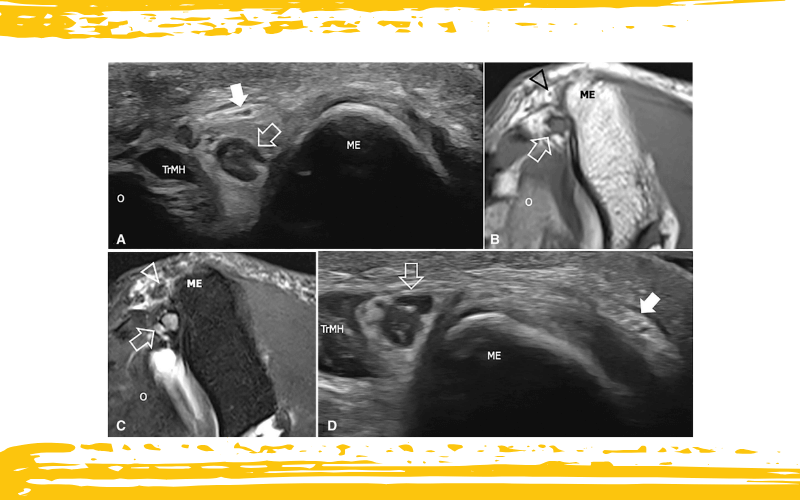

Chasquido del nervio cutáneo medial del antebrazo (MCNF) en un paciente con síndrome del túnel cubital y parestesias ocasionales en la cara medial del antebrazo.

A. La ecografía obtenida a nivel del surco epitroclear durante la extensión del codo y D la misma imagen obtenida durante la flexión máxima del codo muestran una rama del MCNF (flecha) desplazándose en resalte (“snapping”) sobre el epicóndilo medial del húmero (ME). Obsérvense los sutiles cambios que afectan al epineurio de esta pequeña rama, que aparece engrosada e hiperecogénica como consecuencia del roce contra el epicóndilo medial. El nervio cubital tumefacto (flecha delineada) mantiene su posición dentro del túnel cubital durante la maniobra dinámica, pero aparece comprimido contra el epicóndilo medial por la cabeza medial del tríceps (TrMH).

B. La imagen axial ponderada en T1 tSE correspondiente y C la imagen axial ponderada en T2 tSE con supresión grasa muestran la rama del MCNF (punta de flecha) inmersa en un área de edema de partes blandas, caracterizada por hiperintensidad de señal en la secuencia sensible a líquido. En la RM, el nervio cubital aparece aumentado de tamaño y presenta mayor intensidad de señal en la secuencia ponderada en T2, en concordancia con compresión neural y acumulación de fluido intraneural.

Ol: olécranon.